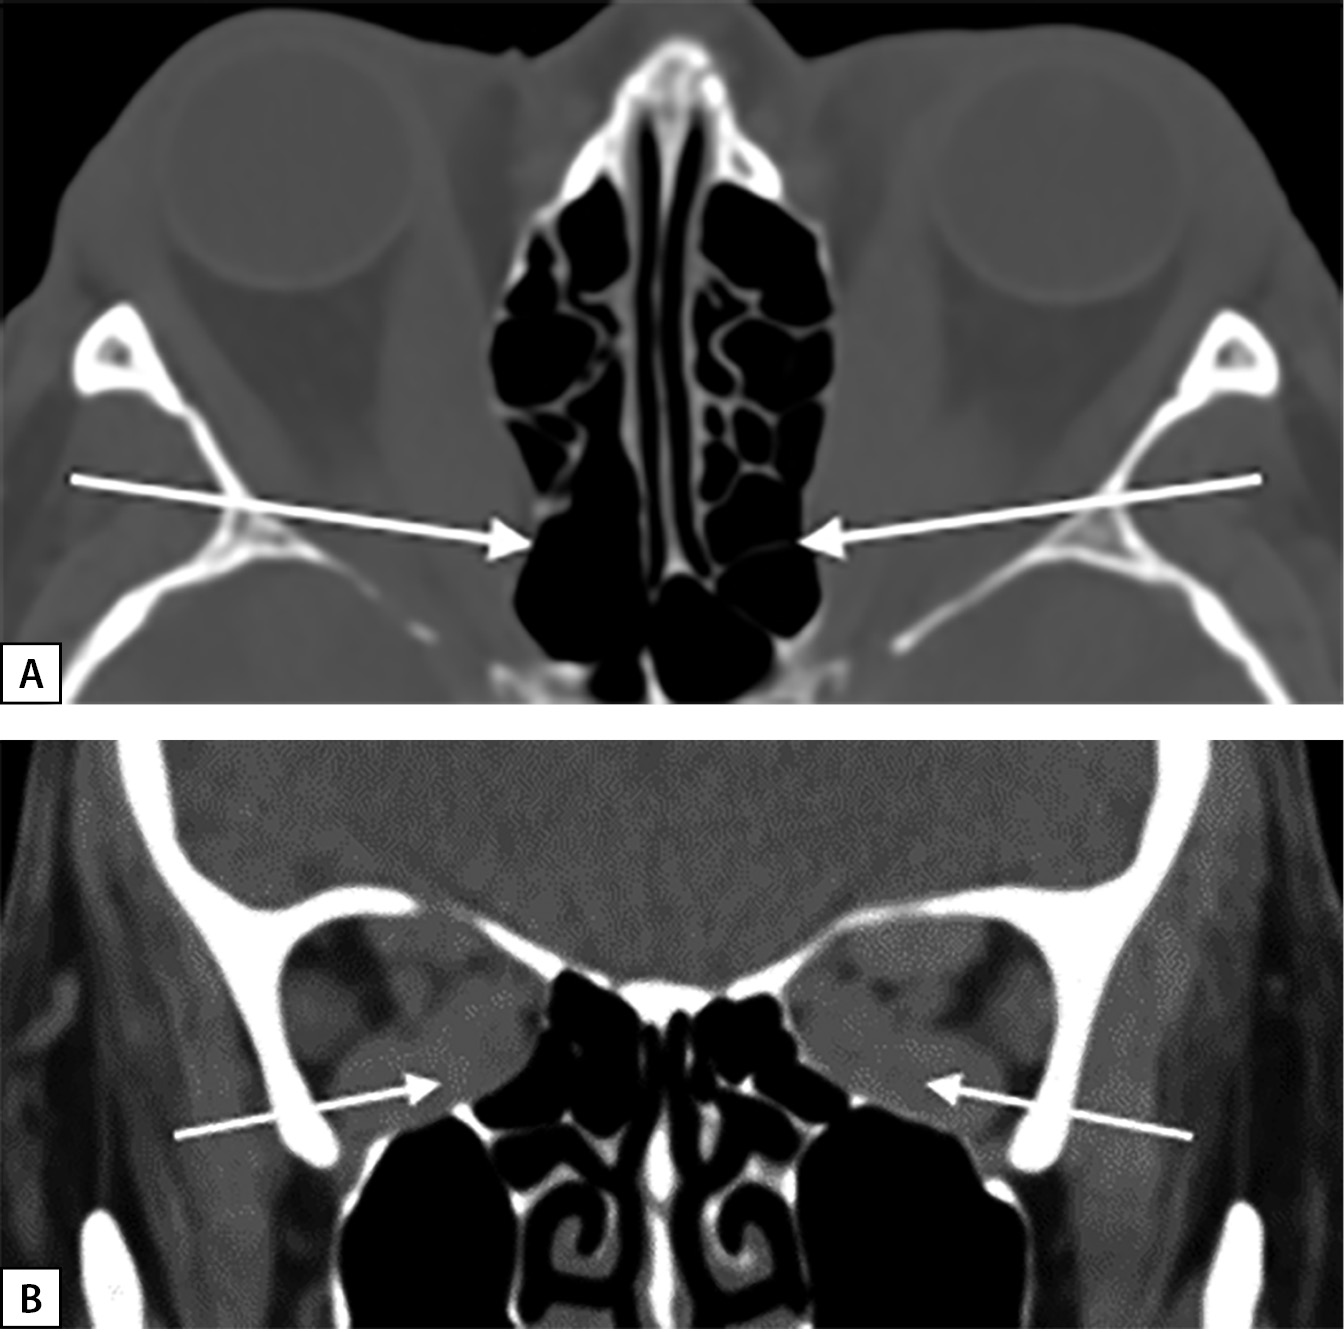

В октябре 2018 г. после отмены метилпреднизолона отмечена значительная отрицательная динамика. При проведении мультиспиральной компьютерной томографии (МСКТ) выявлен синдром вершины орбиты, или «апикального сгущения«, когда глазодвигательные мышцы сдавливают зрительный нерв (рис. 1, А, В). При обследовании в ФГБНУ «НИИ глазных болезней» поставлен диагноз: ЭОП крайне тяжелой степени, оптическая нейропатия с двух сторон, рестриктивное вертикальное косоглазие с горизонтальным компонентом. Бинокулярное двоение. Гипертропия слева. Эзотропия слева.

Рисунок 1. МСКТ орбит пациентки А.:

А — увеличение медиальных прямых мышц.

Деформация медиальной стенки в задней части,

больше выраженная справа

(аксиальная проекция), белые стрелки;

В — апикальный синдром.

Увеличение медиальных, нижних и верхних прямых мышц

(корональная проекция), белые стрелки.